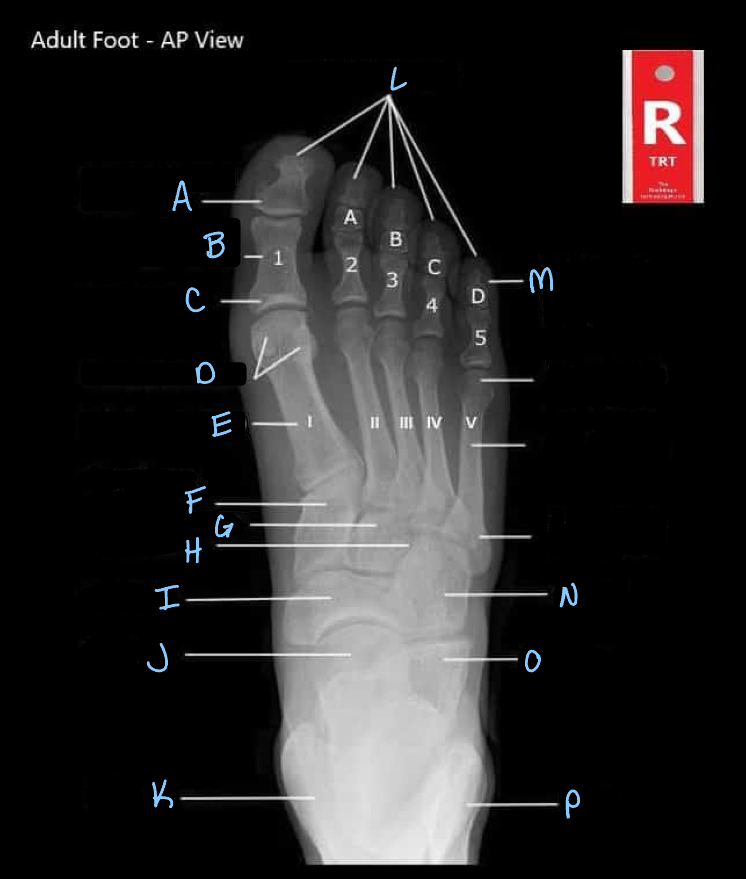

15

What is A?

interphalangeal joint

16

What is B?

proximal phalanges

17

What is C?

metatarsophalangeal joints

18

What is D?

sesamoid bones

19

What is E?

20

Q

A

medial cuneiform

21

What is G?

intermediate cuneiform

22

What is H?

lateral cuneiform

23

What is I?

24

What is J?

25

What is K?

tibia

26

What is L?

distal phalanges

27

What is M?

intermediate phalanges

28

What is N?

cuboid

29

What is O?

calcaneum

30

What is P?

fibula